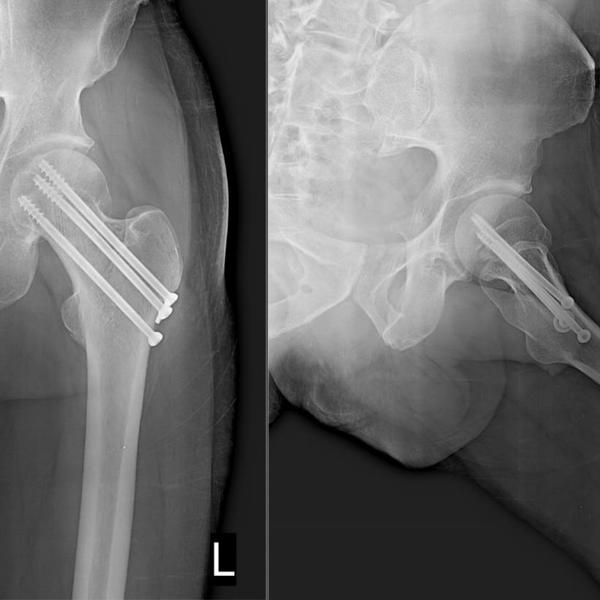

View DetailsSuccessful Hip fracture fixation surgery in Greater Noida/ Noida extension

Successful Hip fracture fixation surgery in Greater Noida/ Noida extension